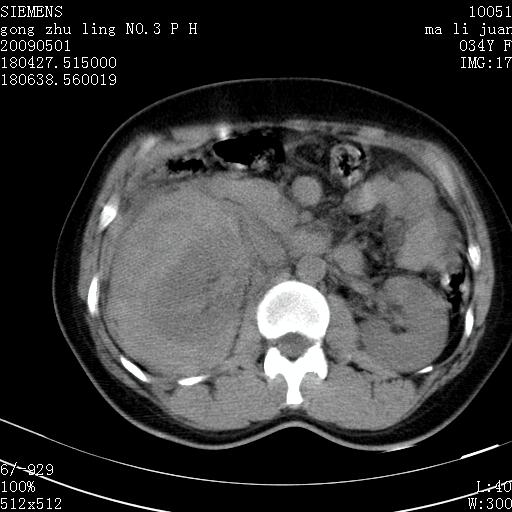

标题: CT19733:右肾碎裂

青年女性,骑摩托车摔伤。

右肾碎裂伤,包膜下血肿。

术中仅见右肾碎裂,肾蒂血管未见断裂。

支持右肾碎裂伤,包膜下血肿。

支持右肾破裂伴包膜下血肿。